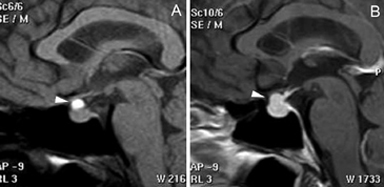

En el caso de los microadenomas, al ser tumores funcionantes, el cuadro clínico y de laboratorio ayuda a definir la localización de la lesión. La glándula pituitaria, considerando el pequeño tamaño de los tumores, puede mostrar forma y volumen normal. En un 20-25% de los casos no se logra demostrar los microadenomas menores de 3 mm, lo que aumenta al 40% en el casos de los adenomas productores de ACTH, en que los exámenes falsos negativos son más frecuentes36-38 (Figuras 11A, 11B, 11C y11D). En este grupo de pacientes es fundamental la utilización de protocolos de examen que incluyan cortes finos coronales de 1 mm en secuencias ponderadas en T1 antes, durante y después de la inyección de Gadolinio, para asegurar la detección de los adenomas, los cuales se contrastan en general más tardíamente que la glándula normal39-41 (Figuras 12A y 12B).

Figura 11A. Microadenoma pituitario productor de ACTH, corte coronal, secuencia T1w, muestra señal homogénea en la hipófisis. B. corte coronal (secuencia dinámica T1w con Gadolinio); se observa nódulo hipointenso de 3 mm (que aun no se refuerza) en cuadrante inferolateral izquierdo de la hipófisis (punta de flecha). C. corte coronal, secuencia tardía T1w con Gadolinio, muestra refuerzo heterogéneo de la glándula, no es posible precisar la ubicación del tumor. D. corte coronal, secuencia volumétrica SPGR T1w con Gadolinio de 1 mm de espesor, que muestra claramente la ubicación del tumor (punta de flecha). Esta secuencia ha mostrado mejores resultados en la evaluación de la enfermedad de Cushing.